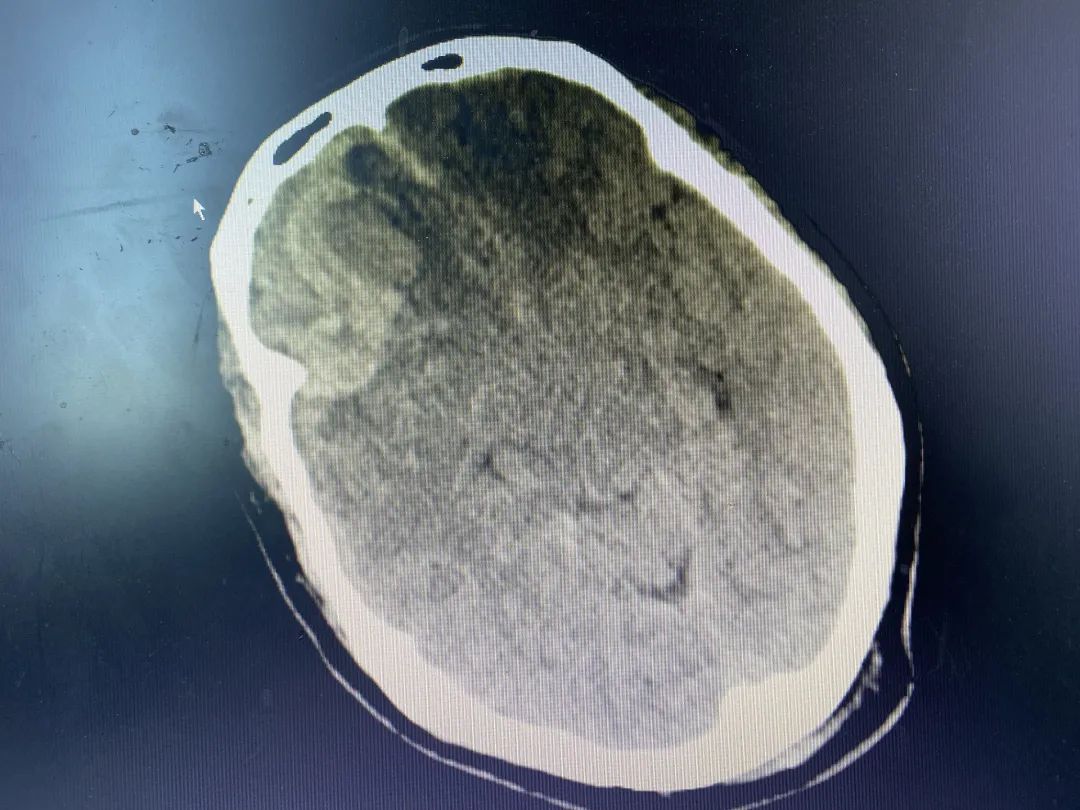

神經(jīng)外科值班醫(yī)師會(huì)診后發(fā)現(xiàn)患者出血量大、腦疝形成、神志呈昏迷狀態(tài),病情十分危重,亟需手術(shù)治療。我院神經(jīng)外科立即給予減輕腦水腫,并與福醫(yī)大附二院神經(jīng)外科當(dāng)值專家取得聯(lián)系,共同研討患者病情。征得家屬同意后,在福醫(yī)大附二院當(dāng)值專家趕往我院的同時(shí),神經(jīng)外科積極做好術(shù)前準(zhǔn)備,專家到位后第一時(shí)間將患者送入手術(shù)室予急診全麻下行“右額葉腦內(nèi)血腫清除術(shù)+右額顳頂硬腦膜下血腫清除術(shù)+顱骨去骨瓣減壓術(shù)”,術(shù)后安返ICU進(jìn)一步治療,復(fù)查CT,血腫大部分清除。